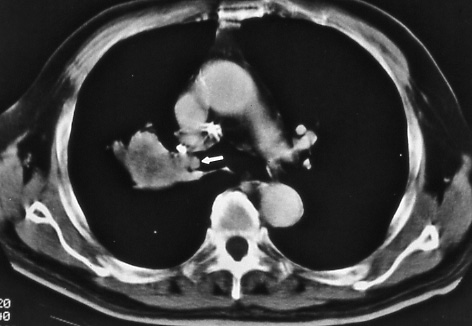

Fig. 12b:

Computed tomographic scan of the chest confirms tumor in the right main stem bronchus within 2 cm of the carina (white arrow), T3 disease.